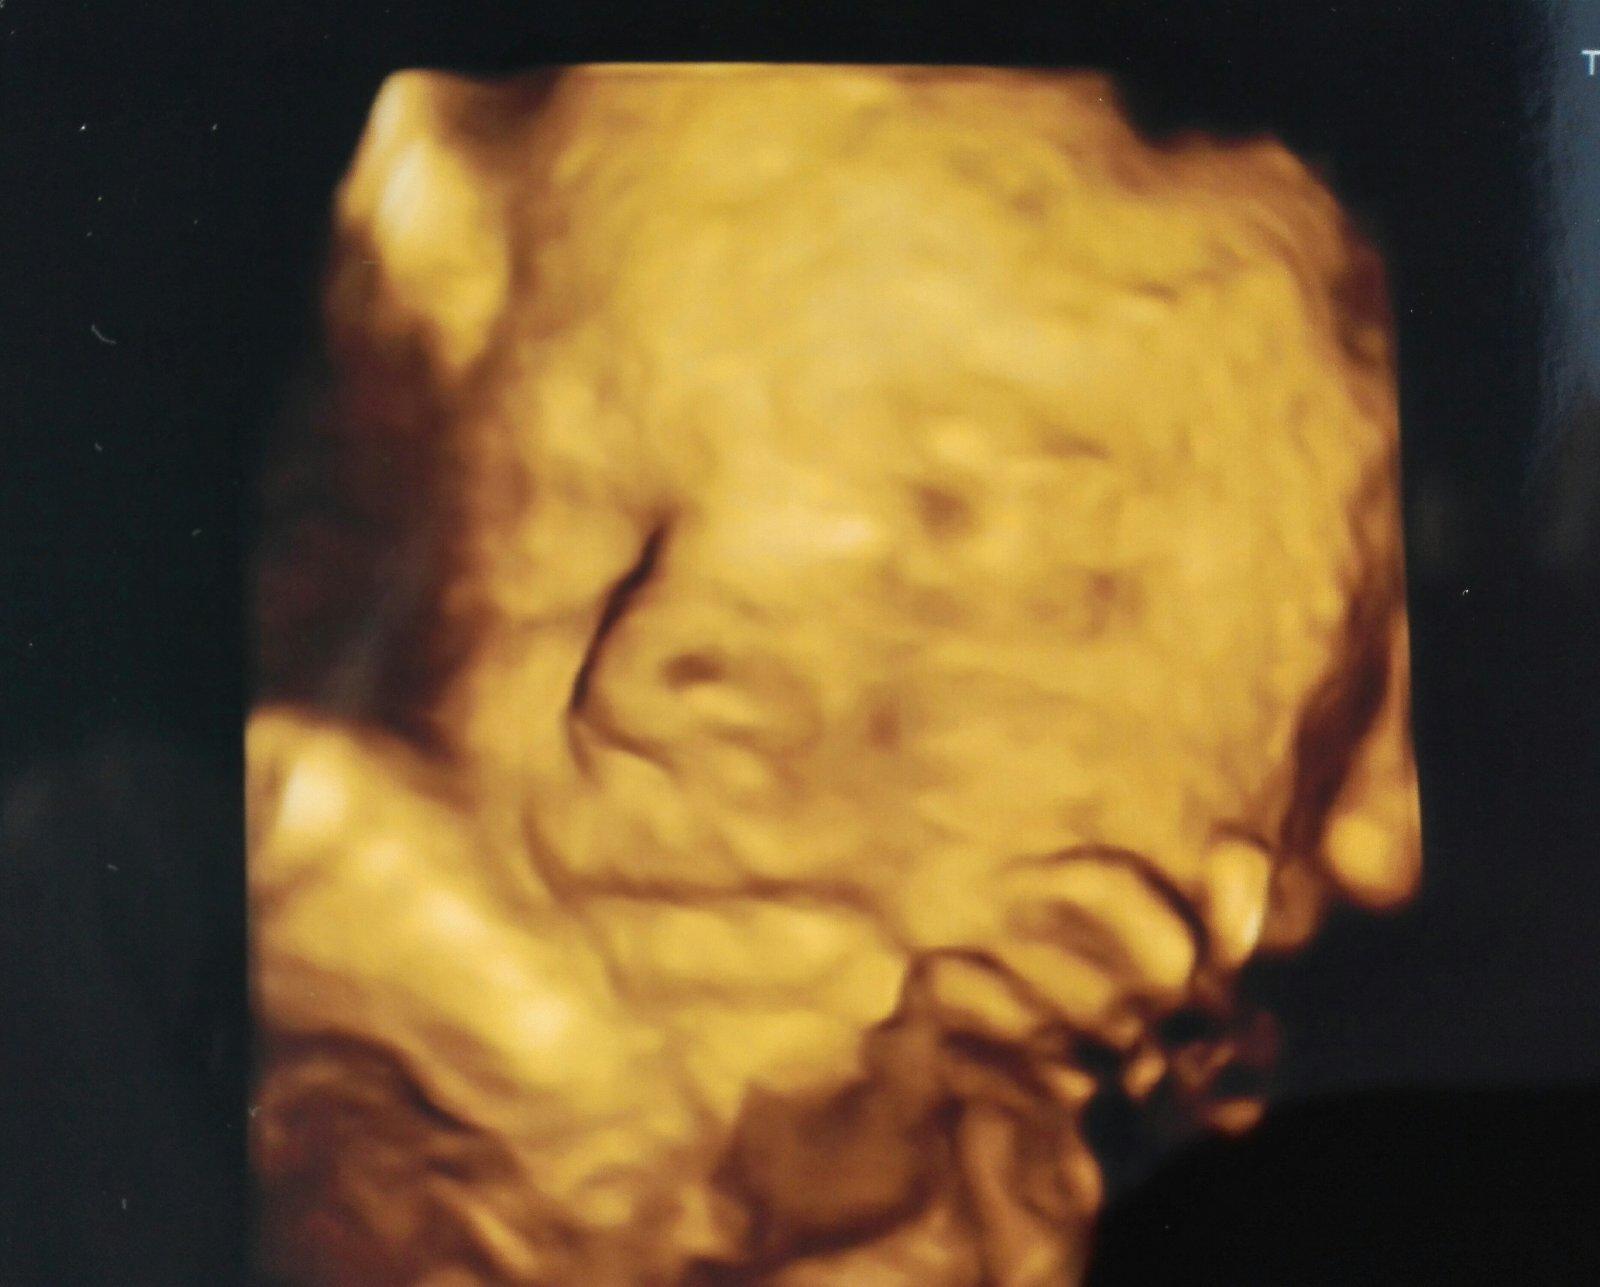

Holky, tak dneees 🙏🙏🙏 snad se ukáže 😀

Kluk! Je to tam... 💪😁 mě se splnil sen.. 😁

@rosalline cim? Pohlavim? 😃 chlapecek to bude 😊